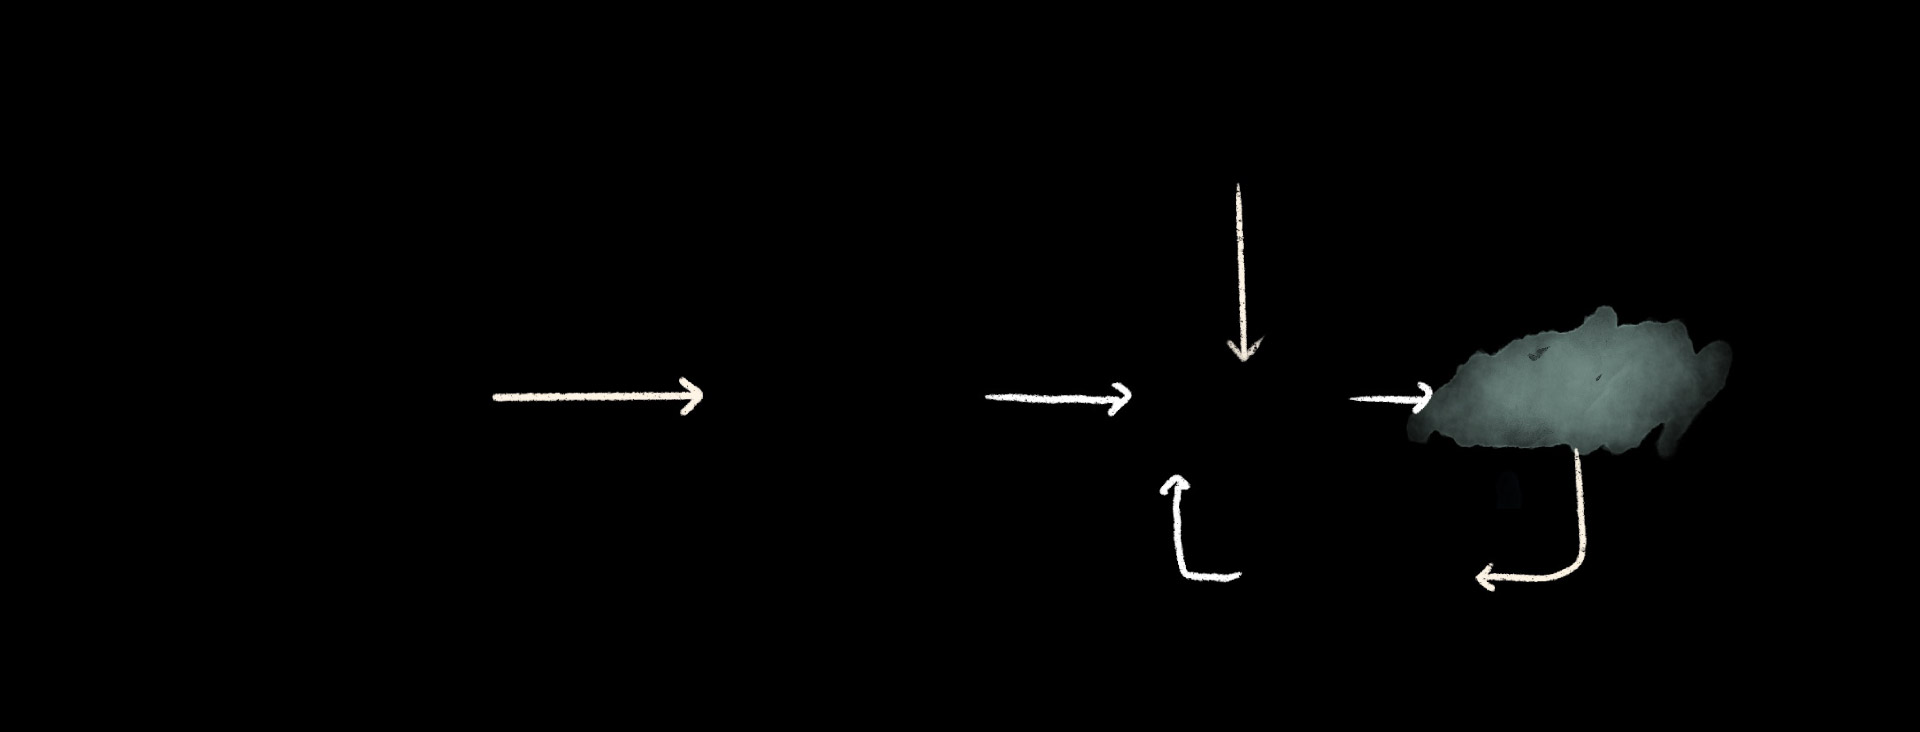

With hospitals over capacity and struggling to keep the lights on, they cannot handle another public health crisis.

Hospital

Gaza’s most vulnerable will be the worst affected “like children, like the elderly, pregnant women, people with disabilities,” Schillinger said.

In conflict areas, children under the age of 5 are 20 times more likely to die of diarrheal disease than to violence, according to UNICEF. Medications have run out.